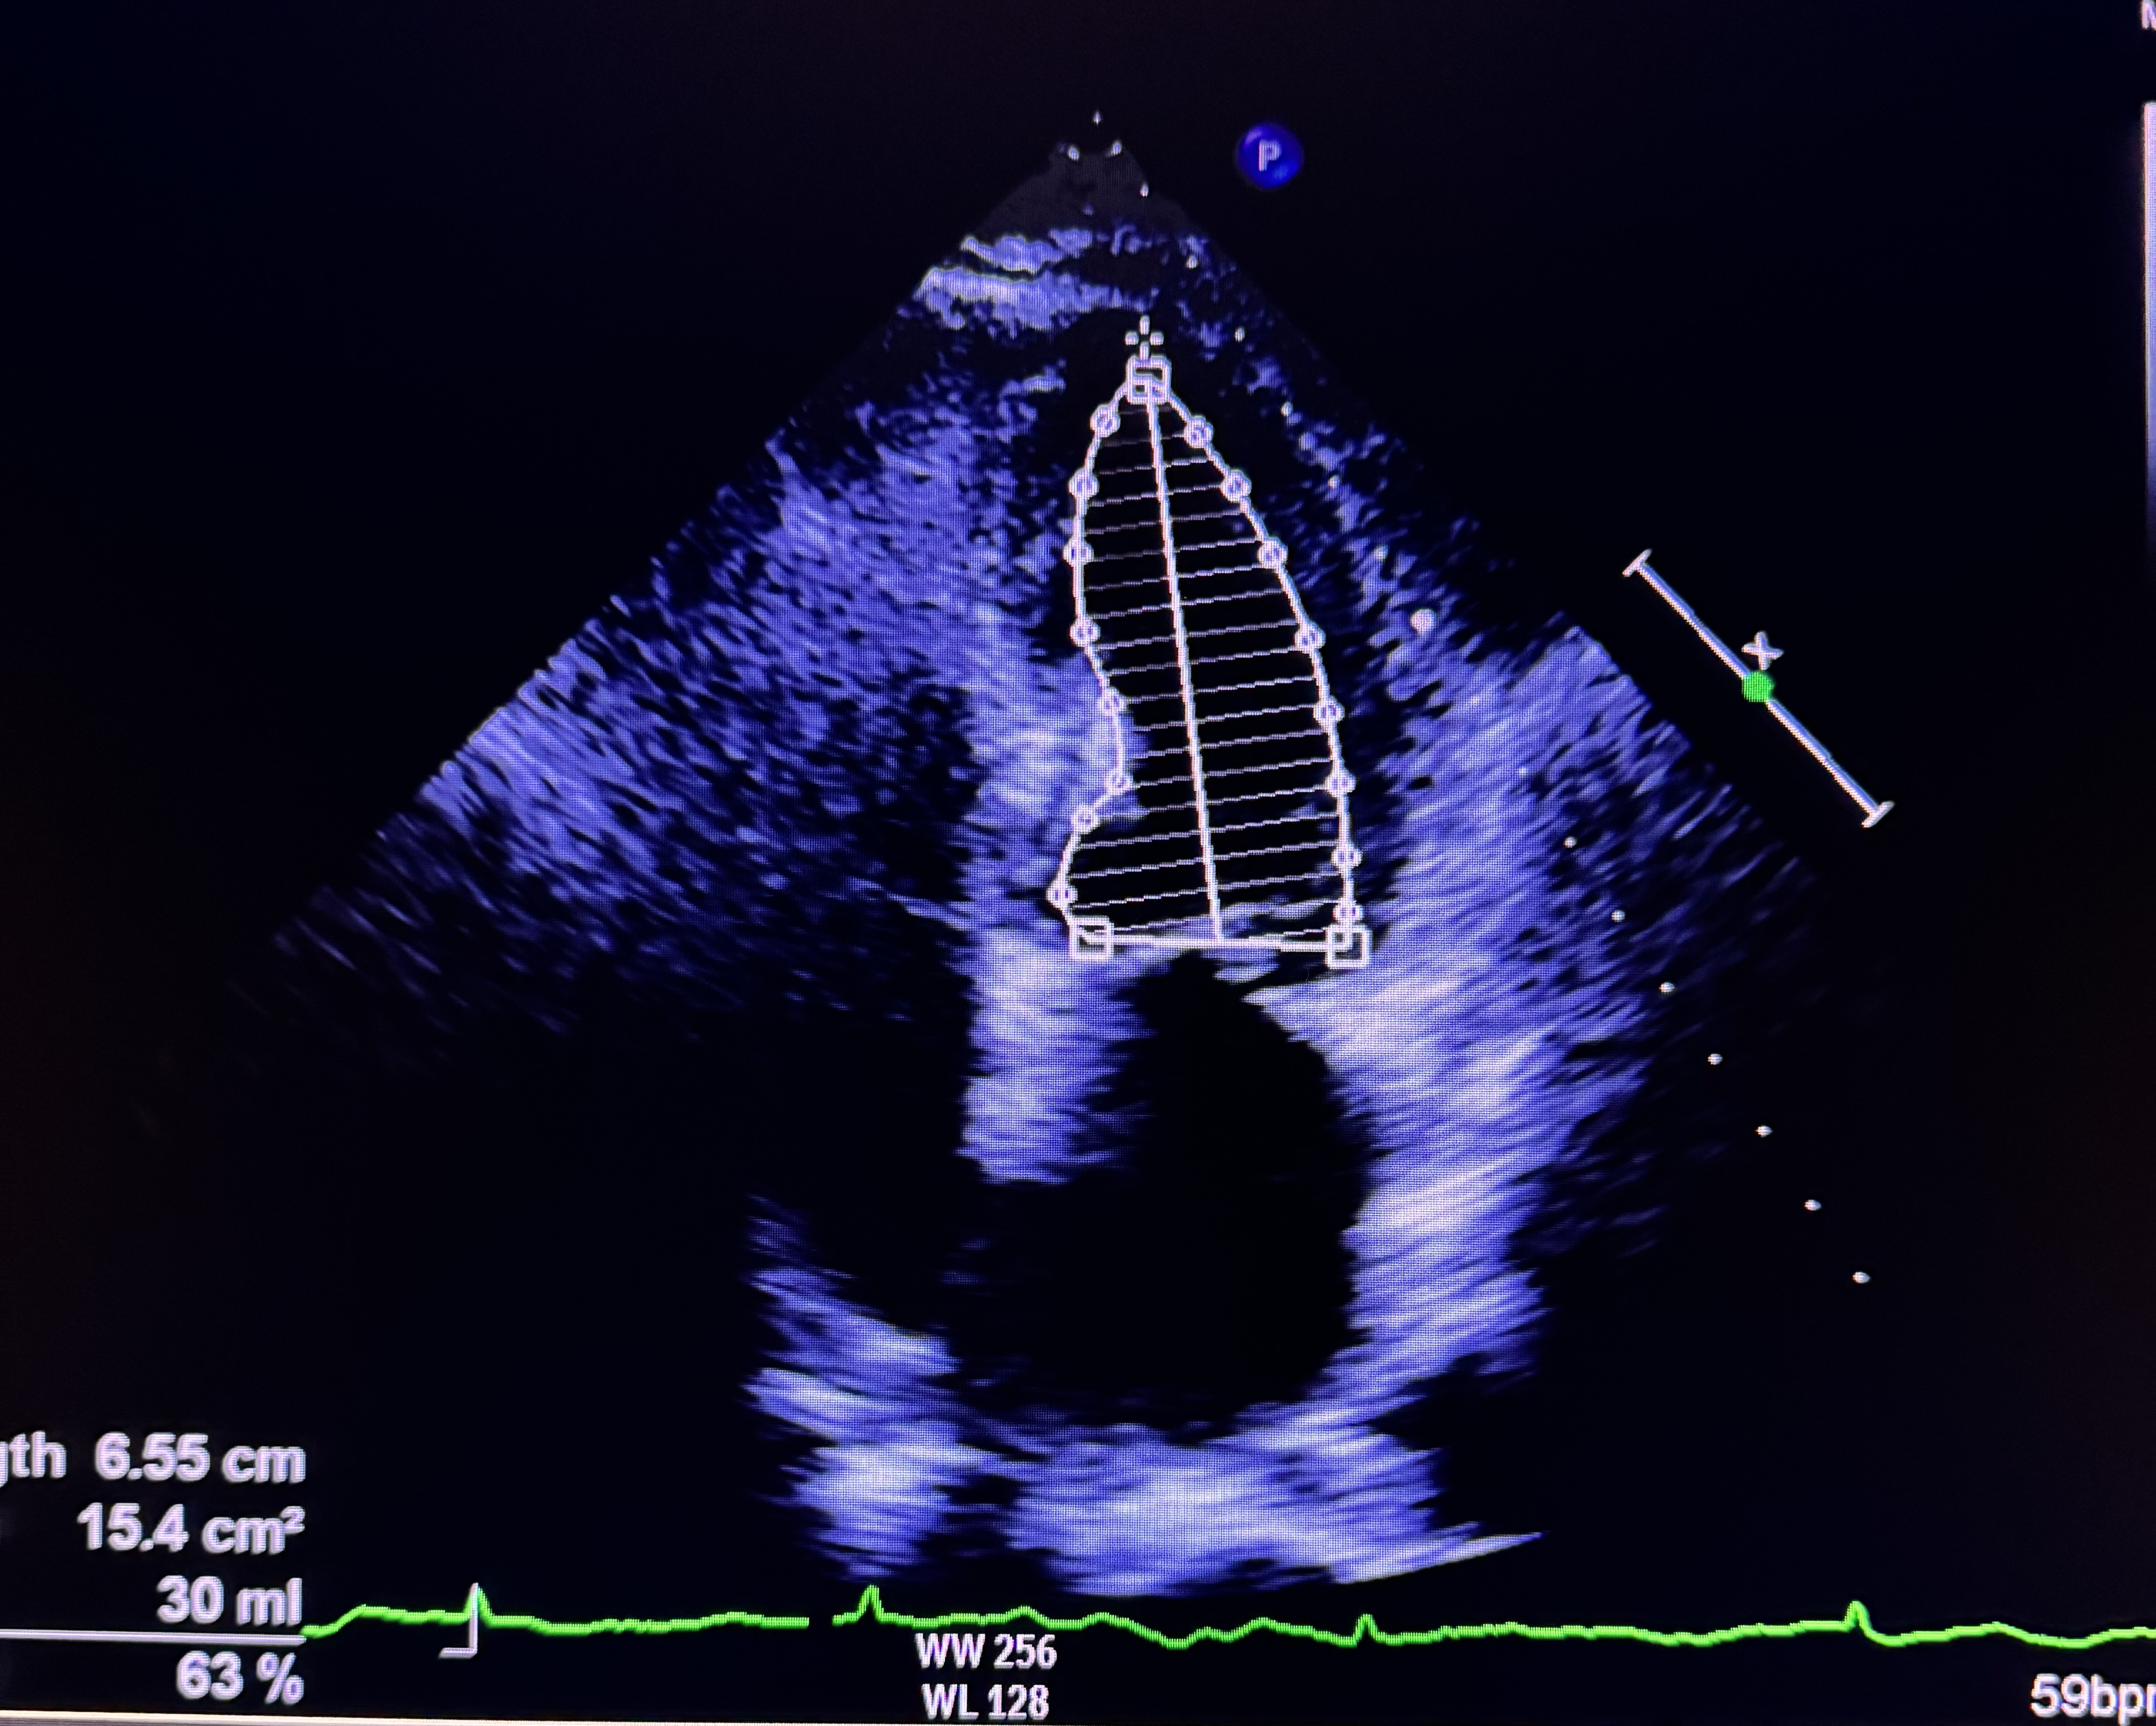

Relevant Test Results Prior to Catheterization

Cardiac Hs troponin was normal (20.4). Electrocardiogram demonstrated sinus rhythm 65 beats/min with isolated T inversion on lead IIIEchocardiogram demonstrated normal left ventricular systolic function with ejection fraction of 70%. Diastolic function corresponded with grade 1 dysfunction and no wall motion abnormalities. Her left ventricular size was normal with no evidence of mechanical complication of acute coronary syndrome. These informations led to the diagnosis of unstable angina